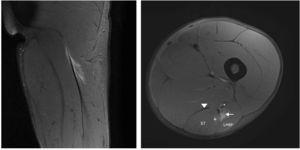

Figura 1 Les imatges coronal i axial en T2 amb supressió de greix de l’isquiotibial esquerre mostren trencament parcial de fibres a la UMT proximal de CLBF representades per una àrea d’alta intensitat de senyal adjacent a la UMT (fletxa). S’observa també ruptura d’algunes fibres del semitendinós (+). Ventre muscular semitendinós (ST), cap proximal del bíceps femoral llarg (long head biceps femoris [LHBF]), tendó semimembranós (punta de fletxa) i nervi ciàtic (*). En el tall coronal s’observa edema muscular de patró de ploma d’au.

Un jugador de futbol professional de divuit anys sofrí el mateix tipus de dolor en les mateixes circumstàncies. Els senyals clínics eren totalment similars als del cas dels isquiotibials aguts descrit, però la prova d’RM mostrà imatges diferents (figs. 3 i 4) perquè la lesió estava localitzada al tendó lliure del bíceps femoral. La longitud del tendó lliure fou 8,5 cm i la lesió fou localitzada a 6,5 cm de la tuberositat isquiàtica. Degut al llarg període de recuperació i a un índex elevat de relesió, cal considerar el tractament quirúrgic. Es realitzà l’escissió del teixit cicatricial, incloent-hi el trencament parcial del tendó y la sutura sense tensió del romanent del ventre del bíceps femoral al semitendinós adjacent, amb la finalitat de proporcionar tensió al tendó i reforç amb ancoratge a la tuberositat isquiàtica (figs. 3 i 4).